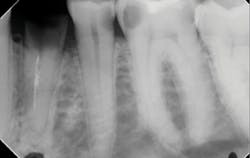

Another reason immediate placement is advantageous is that once the extraction is complete, the hole is usually already in the proper place for the implant. You may have to redirect your osteotomy slightly palatally, mesially, or distally, but the socket serves as an excellent guide for placement. In some cases, especially premolars, you can use an implant with aggressive threads to place without any osteotomy at all. You can engage the mesial and distal walls to achieve primary stability. This greatly shortens the appointment time, lowers risk, and increases patient satisfaction. Figures 1 and 2 show a MorsTorq in site No. 21 that was placed after an atraumatic extraction during my most recent two-day Louisiana Implant Institute course. Note the sharp threading on the MorsTorq, which allows for optimized immediate placement performance.There are some circumstances where immediate placement is not desirable. If the socket is too large to engage the mesial and distal walls and vital anatomical structures are located just apical to the socket, immediate placement is not recommended. Chronically infected sites also present a higher risk for immediate placement. If you can completely rid the socket of all soft tissue and the patient has the appropriate antibiotics onboard, it is possible. However, most of these cases are more predictably treated with early placement (waiting four to six weeks without grafting) or delayed placement (three to six months with grafting).